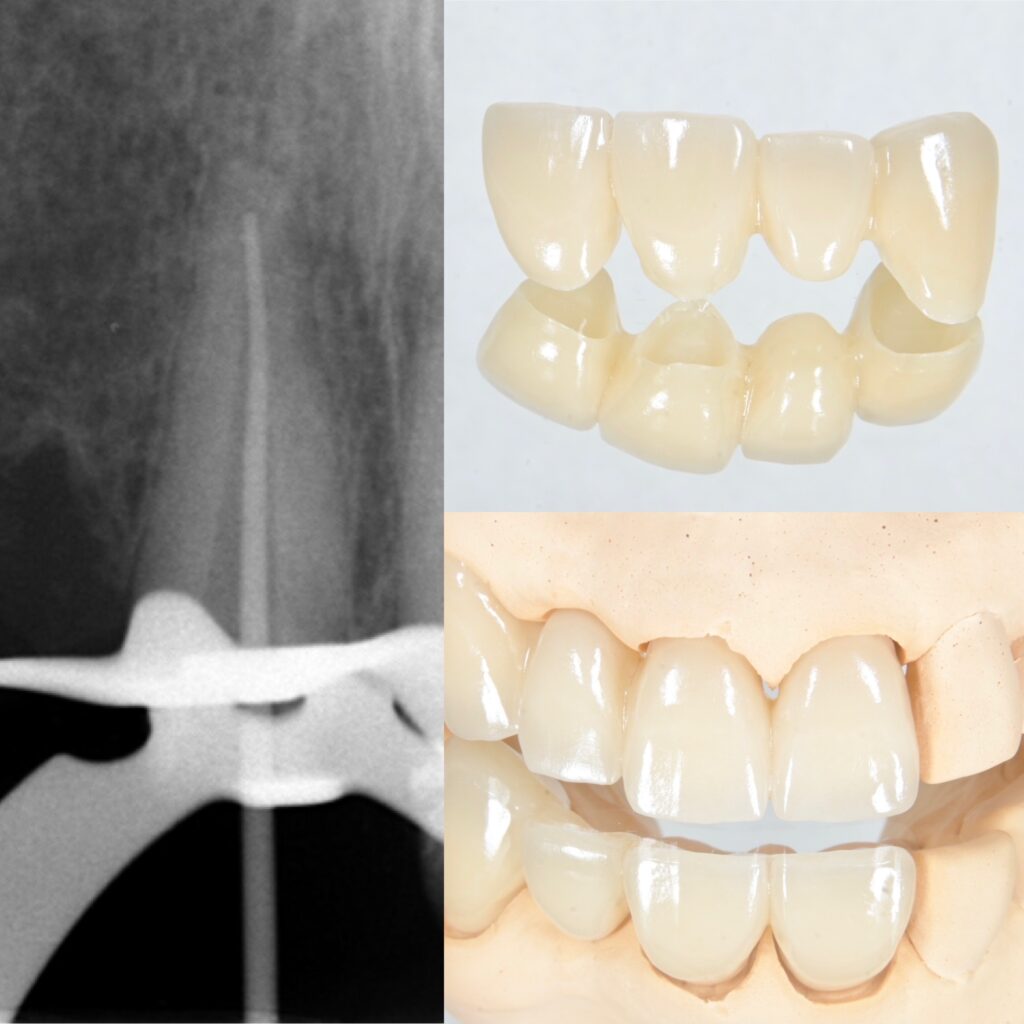

ラバーダムを使用した精密根管治療・完成したセラミック(ジルコニアブリッジ)

3. マイクロスコープを用いた土台作りと歯周組織の安定

セラミックという「美しい家」を建てるためには、強固な「基礎(土台)」が欠かせません。当院ではマイクロスコープ(歯科用顕微鏡)を駆使し、肉眼では見えないレベルでの精密な処置を行います。

- 精密根管治療: 歯の根に問題があれば、どれほど美しい被せ物をしても長持ちしません。拡大視野下で徹底的に細菌を除去し、再発を防ぎます。ラバーダムは必須です。

- 精密な支台歯形成: セラミックを被せる土台の形を、マイクロスコープ下でコンマ数ミリ単位で整えます。

- 歯科技工士の技術: 最終的な色調や透明感、歯の表面の質感は、経験豊富な歯科技工士の手によって、周囲の歯と馴染む「自然な美しさ」へと仕上げられます。